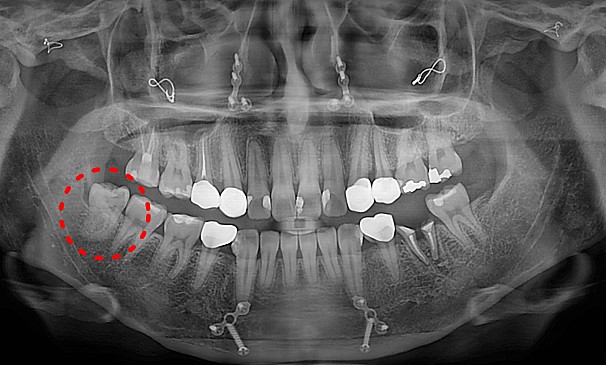

자가치아이식술

김OO님 전후사진 | 치료 기간 : 2주

치료 전